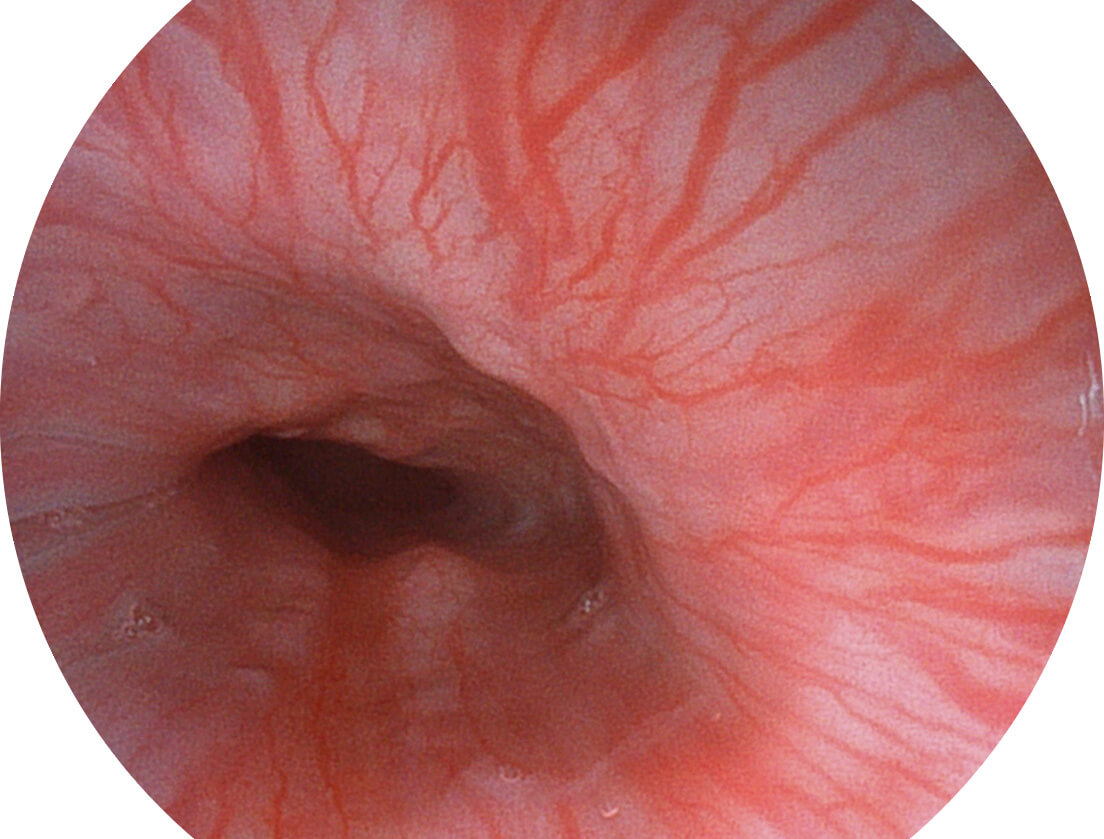

Versatile Intelligent Staining Technology, VIST

强调浅层黏膜结构的同时,保证照明亮度和提升浅层微血管与中层血管颜色对比度,病变边界更清晰。

VIST图像